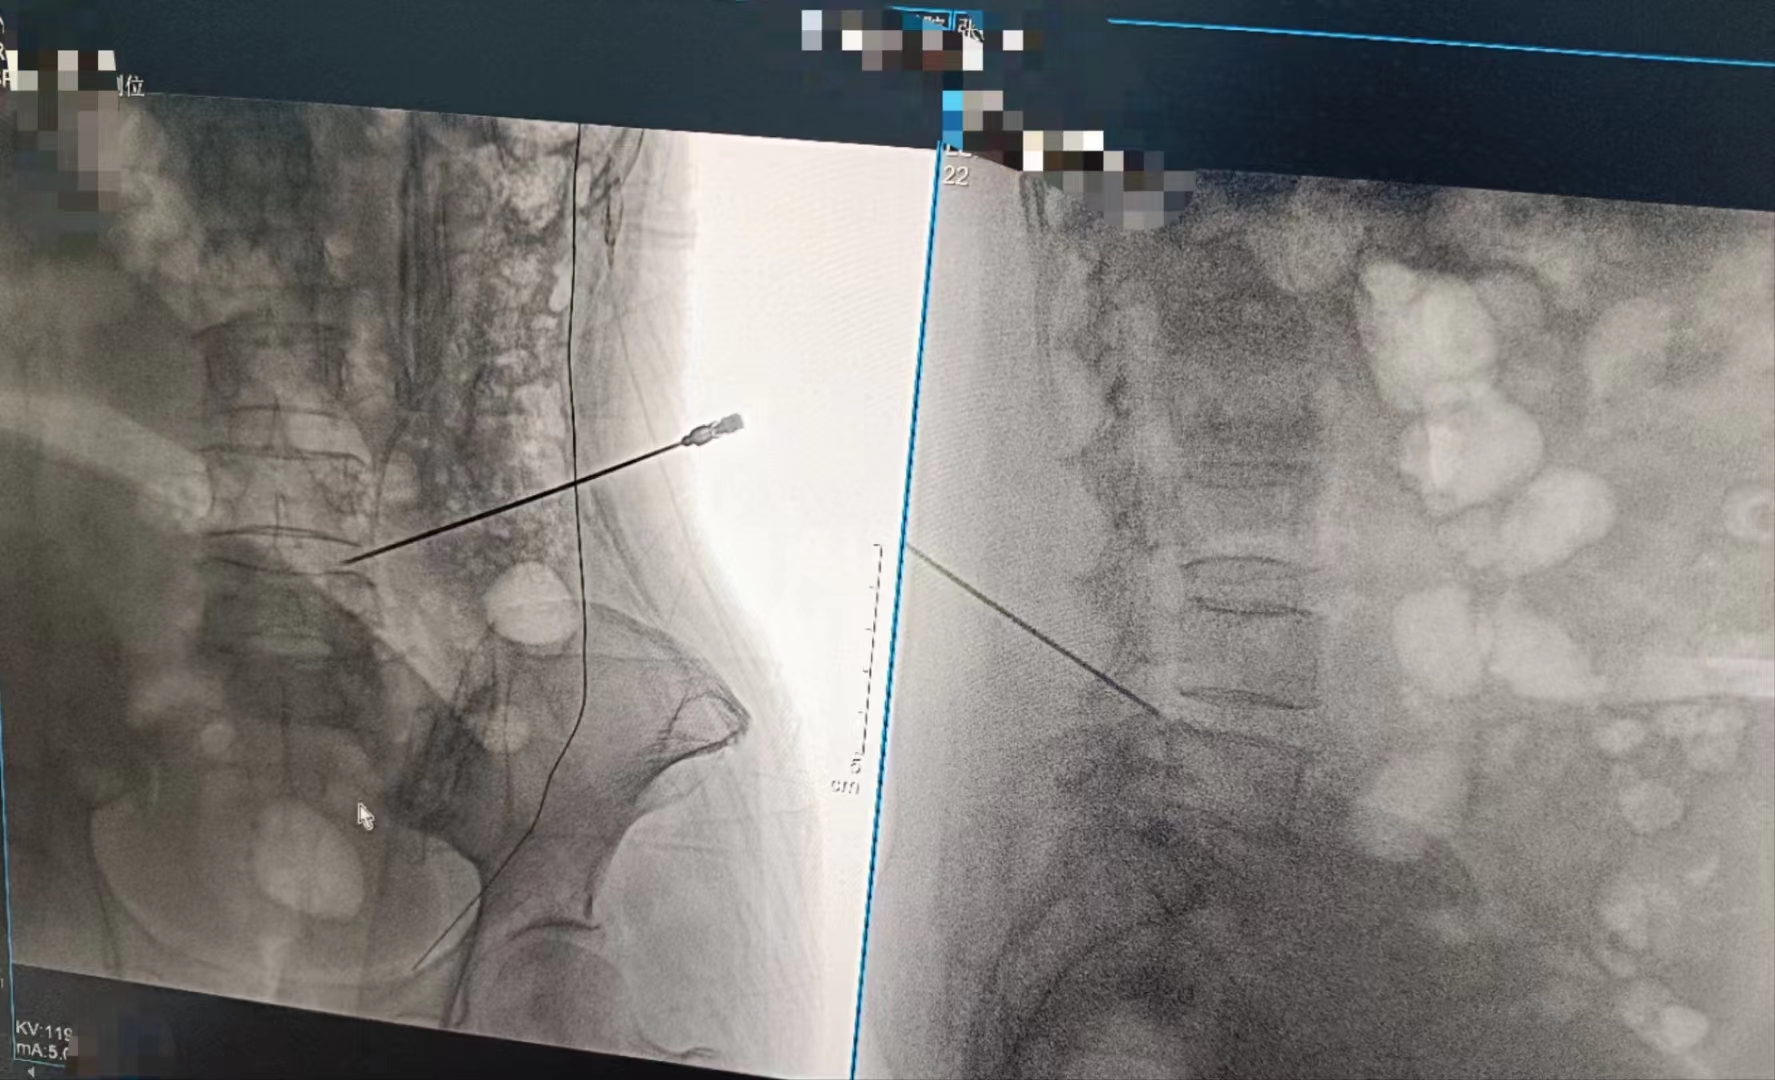

在今日晨曦的溫柔擁抱中,手術(shù)室里上演了一場(chǎng)科技與藝術(shù)的交融。一臺(tái)Dira-DRCF型數(shù)字化X射線攝影設(shè)備,宛如一位靜默的舞者,在手術(shù)醫(yī)生的嫻熟指揮下,翩翩起舞。

醫(yī)生們,身著綠衣,如同守護(hù)生命的使者,他們的雙手靈巧而堅(jiān)定,每一個(gè)細(xì)微的動(dòng)作都透露出對(duì)生命的敬畏與尊重。而這臺(tái)設(shè)備,則是他們手中的魔法棒,透過無形的射線,洞察生命的奧秘。

當(dāng)設(shè)備啟動(dòng),那束柔和的X射線穿過患者的身體,捕捉下每一個(gè)細(xì)微的影像。那一刻,時(shí)間仿佛凝固,所有的目光都聚焦在那塊屏幕上。那里,生命的紋理清晰可見,疾病的陰影無處遁形。

手術(shù)順利完成,當(dāng)醫(yī)生們露出疲憊而欣慰的笑容時(shí),我知道,那不僅僅是勝利的喜悅,更是對(duì)生命的敬畏與珍視。而這一切,都離不開這臺(tái)數(shù)字化X射線攝影設(shè)備的默默付出。